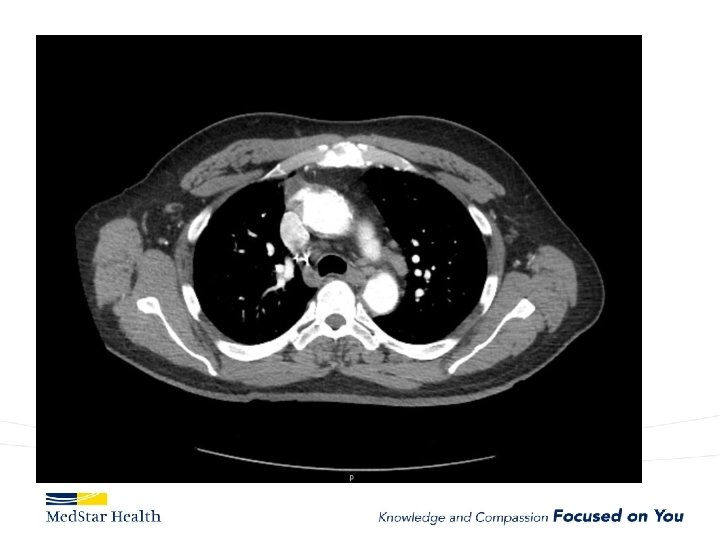

Acute Type B Aortic Dissection • Incidence: 2. 6 -3. 5 per 100, 000 patient-year • Uncomplicated • Complicated – – Malperfusion Rupture Unremitting Pain Uncontrolled HTN

“Uncomplicated” – Type B

Type B Dissection Complicated Uncomplicated Risk TEVAR age, comorbidities Extreme Low Medical Management False Lumen Small, Thrombosed Medical Management Patent/Large(>22 mm), Total Aorta >40 mm TEVAR/adjuncts